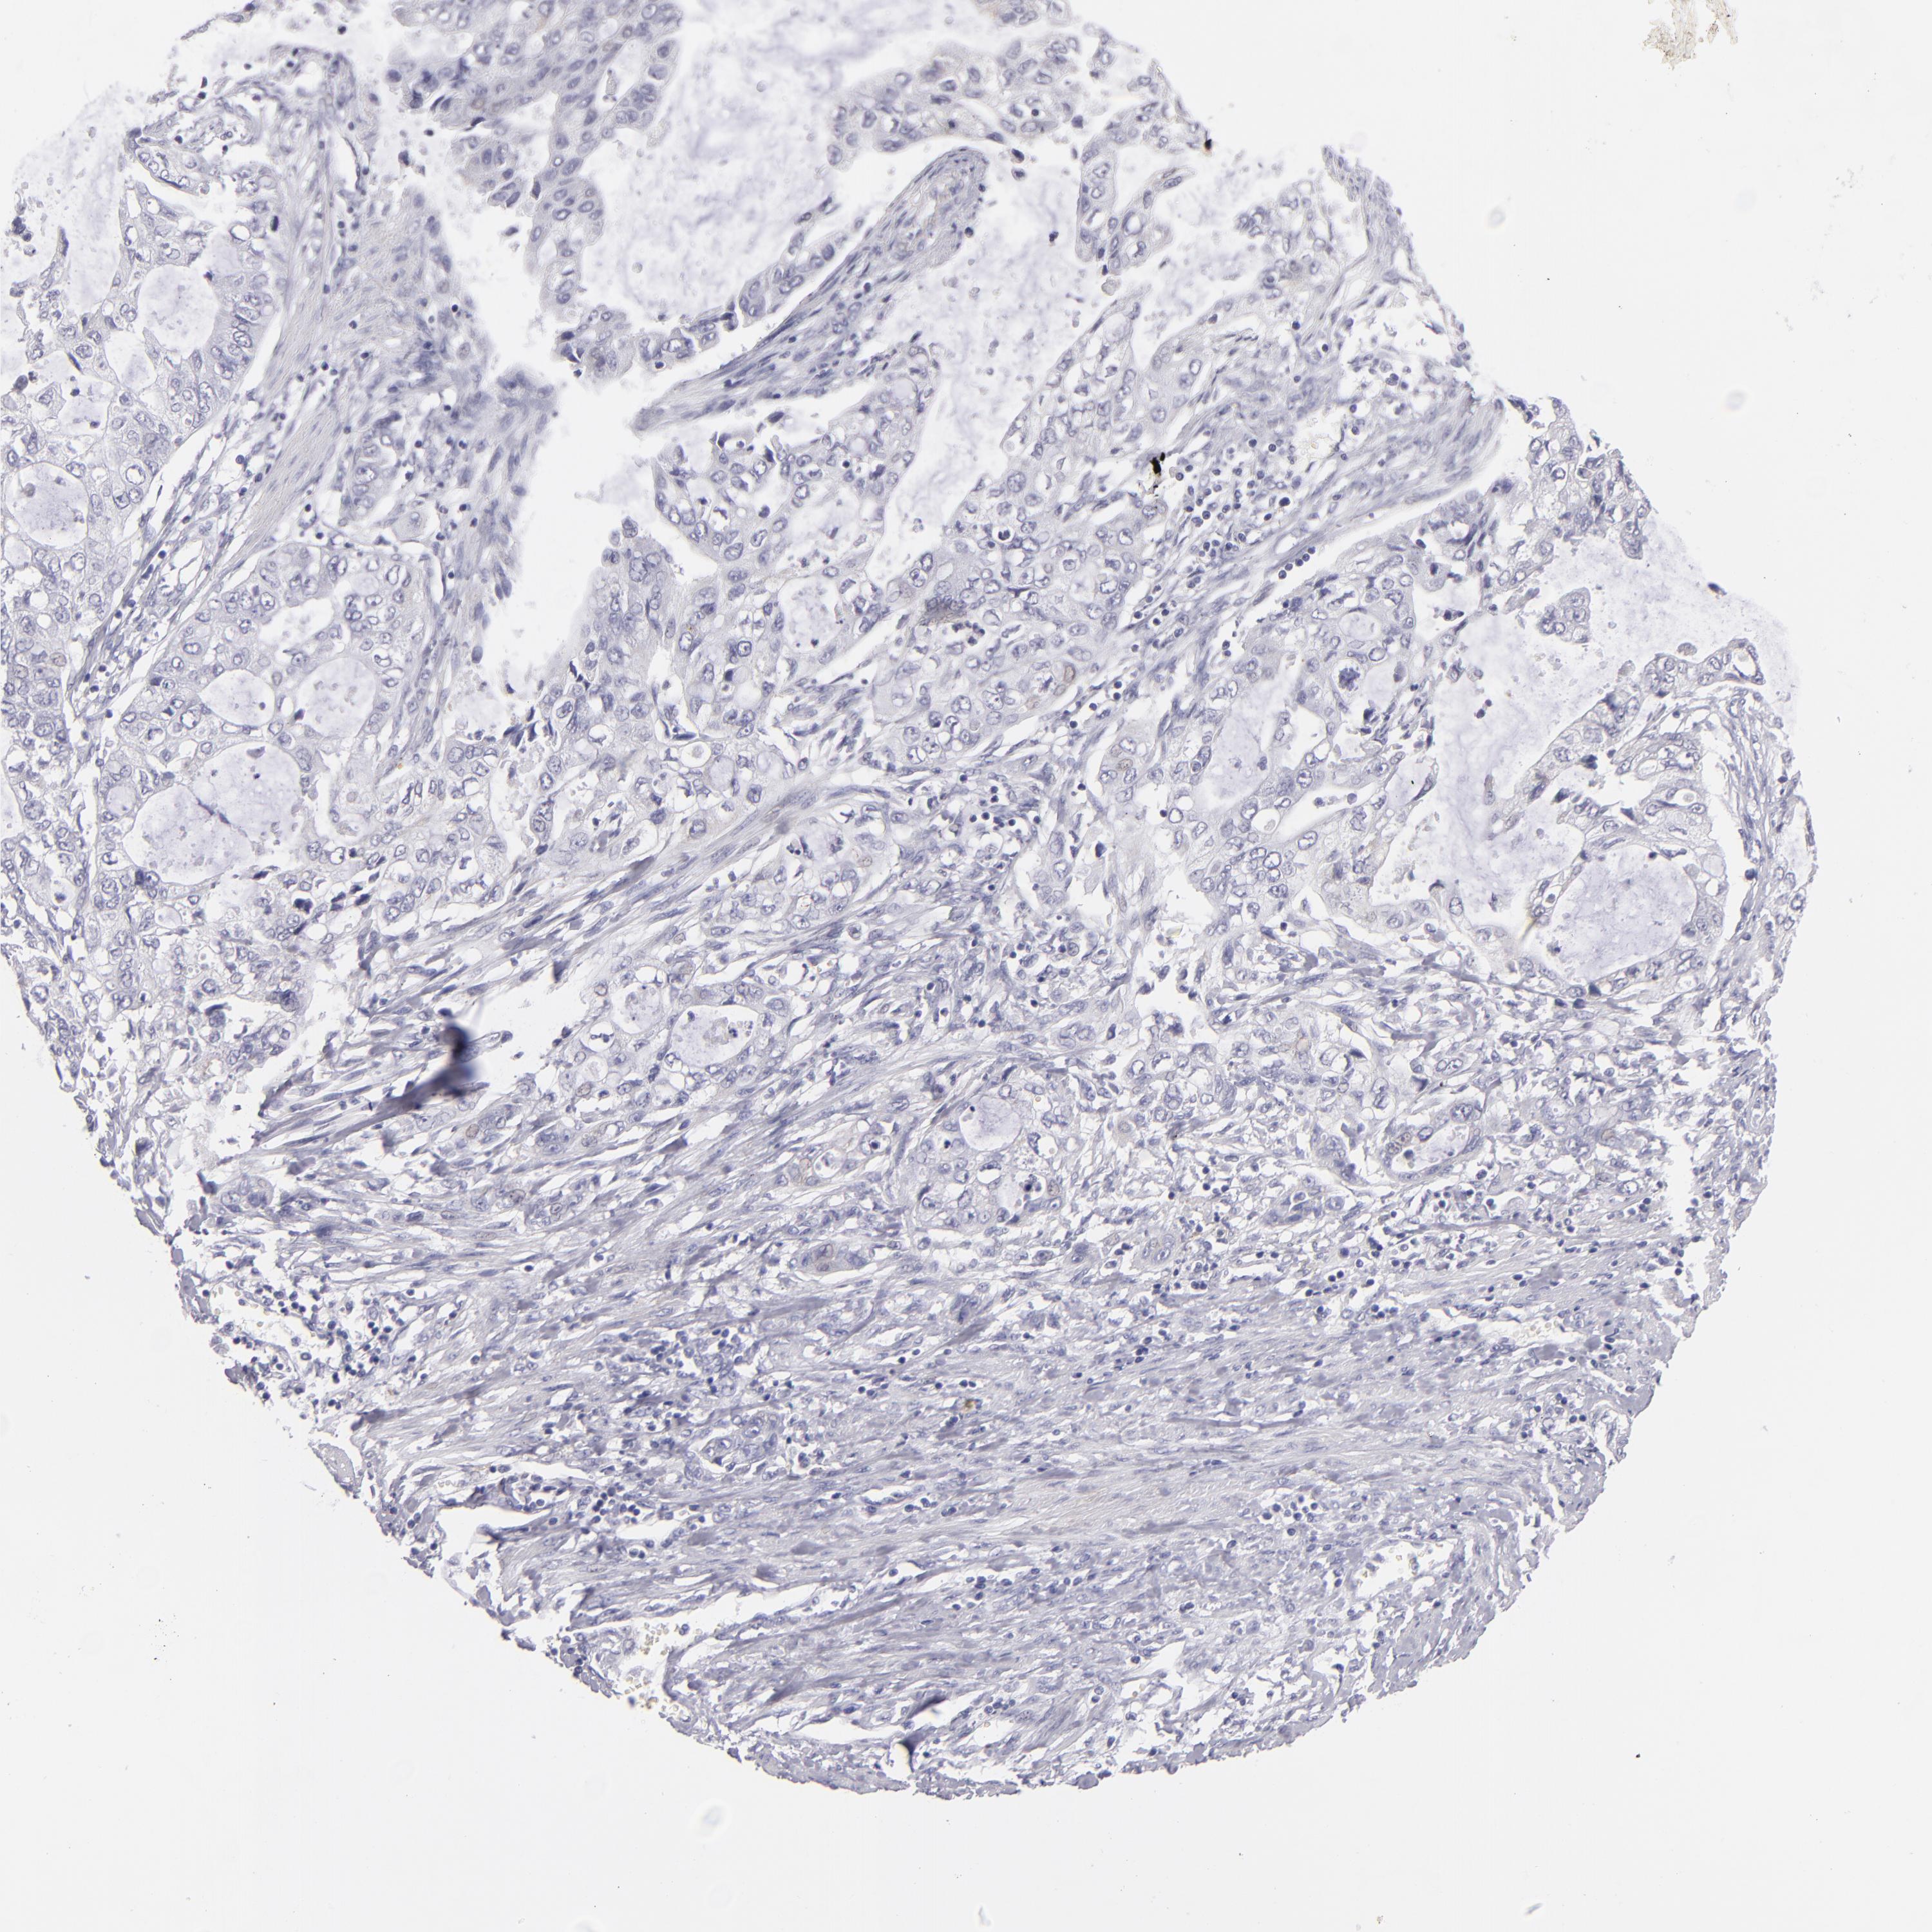

STOMACH CANCER - Protein expressioni

A mouse-over function shows sample information and annotation data. Click on an image to view it in a full screen mode. Samples can be filtered based on level of antibody staining by selecting one or several of the following categories: high, medium, low and not detected. The assay and annotation is described here.

Note that samples used for immunohistochemistry by the Human Protein Atlas do not correspond to samples in the TCGA dataset.

Antibody stainingi

Antibody staining in the annotated cell types in the current human tissue is reported as not detected, low, medium, or high, based on conventional immunohistochemistry profiling in selected tissues. This score is based on the combination of the staining intensity and fraction of stained cells.

Each image is clickable and will lead to virtual microscopy that enables deeper exploration of all samples and also displays staining intensity scores, fraction scores and subcellular localization as well as patient and tissue information for each sample.

Antibody HPA044848

Antibody HPA056897

Antibody CAB002450

Staining

High

Medium

Low

Not detected

Intensity

Strong

Moderate

Weak

Negative

Quantity

>75%

75%-25%

<25%

None

Location

Nuclear

Cytoplasmic/membranous

Cytoplasmic/membranous,nuclear

Adenocarcinoma, NOS

Adenocarcinoma, High grade